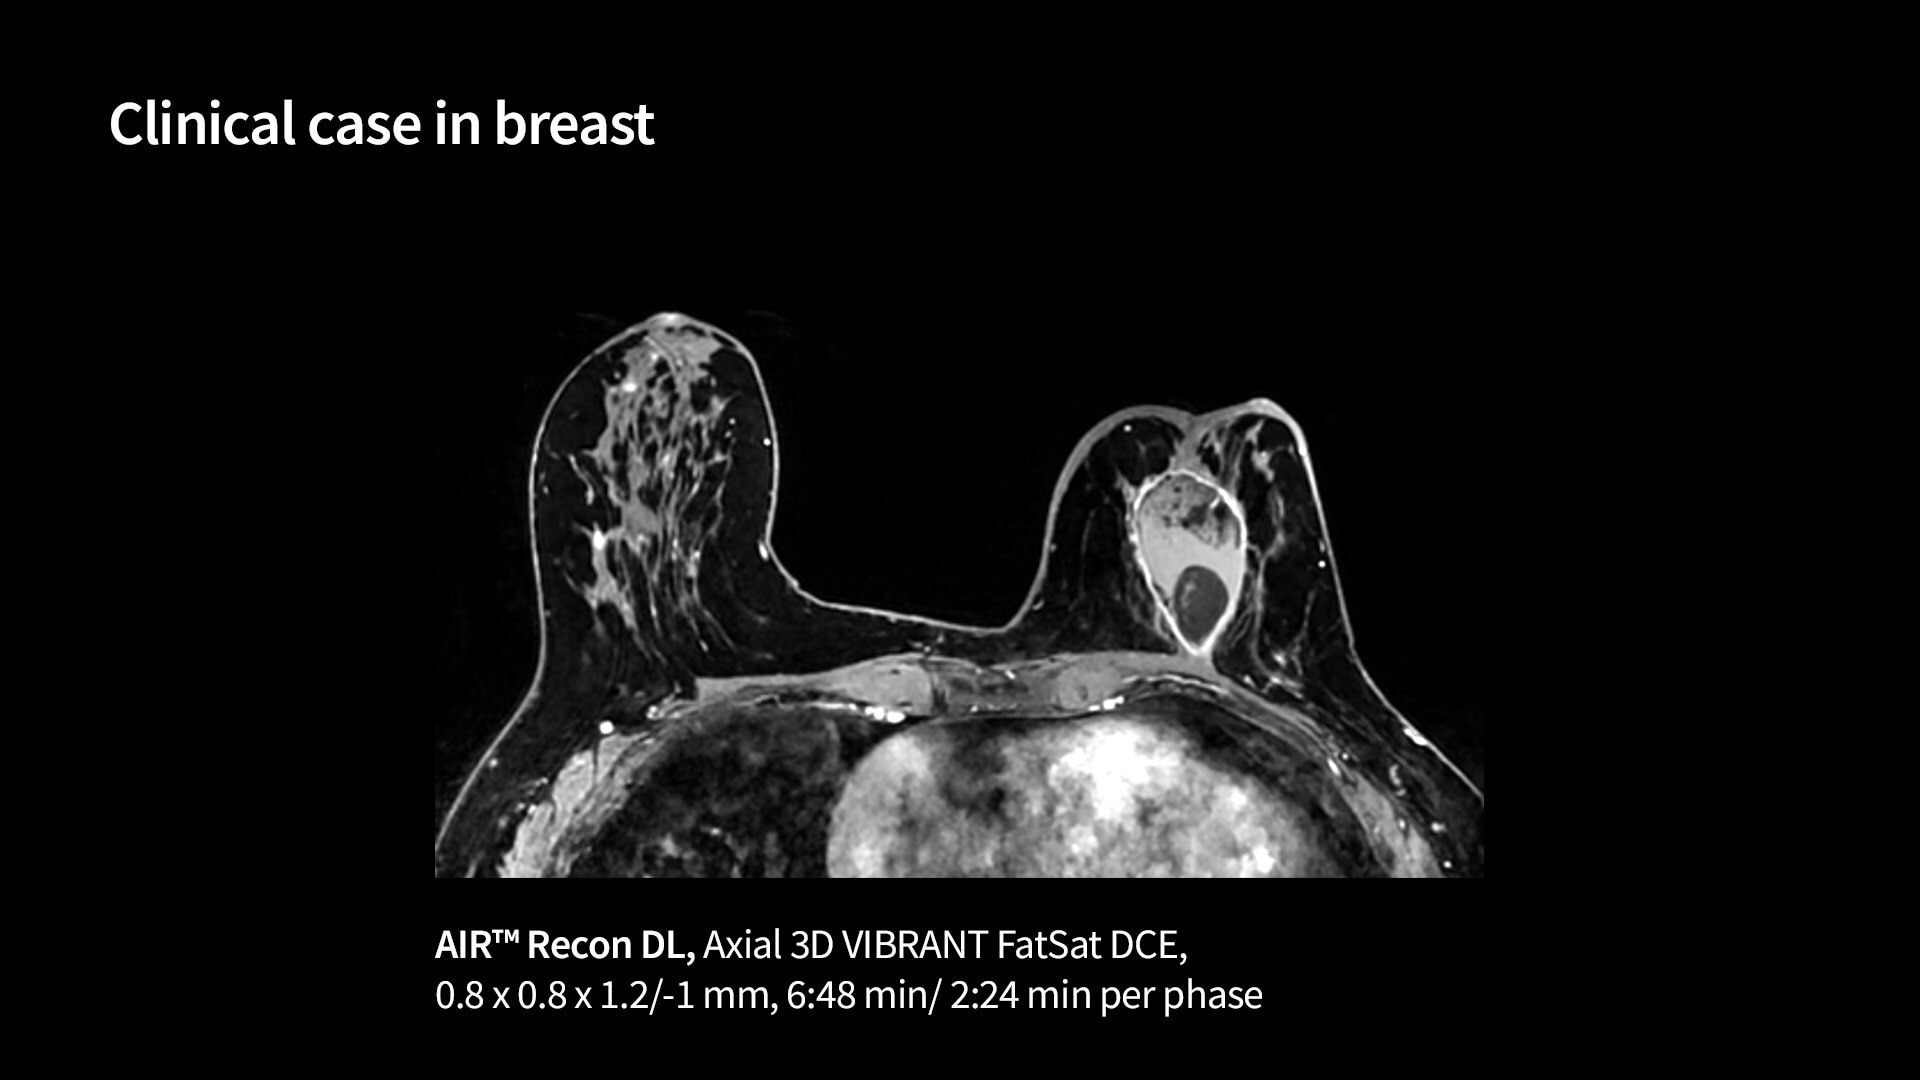

<p>VIBRANT (compatible with AIR Recon DL) &amp; VIBRANT Flex</p>

Read case study ico-caret-right